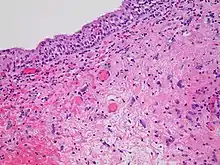

- Epithelial surfaces may sustain damage from radiation therapy.[19] Depending on the area being treated, this may include the skin, oral mucosa, pharyngeal, bowel mucosa, and ureter. The rates of onset of damage and recovery from it depend upon the turnover rate of epithelial cells. Typically the skin starts to become pink and sore several weeks into treatment. The reaction may become more severe during the treatment and for up to about one week following the end of radiation therapy, and the skin may break down. Although this moist desquamation is uncomfortable, recovery is usually quick. Skin reactions tend to be worse in areas where there are natural folds in the skin, such as underneath the female breast, behind the ear, and in the groin.